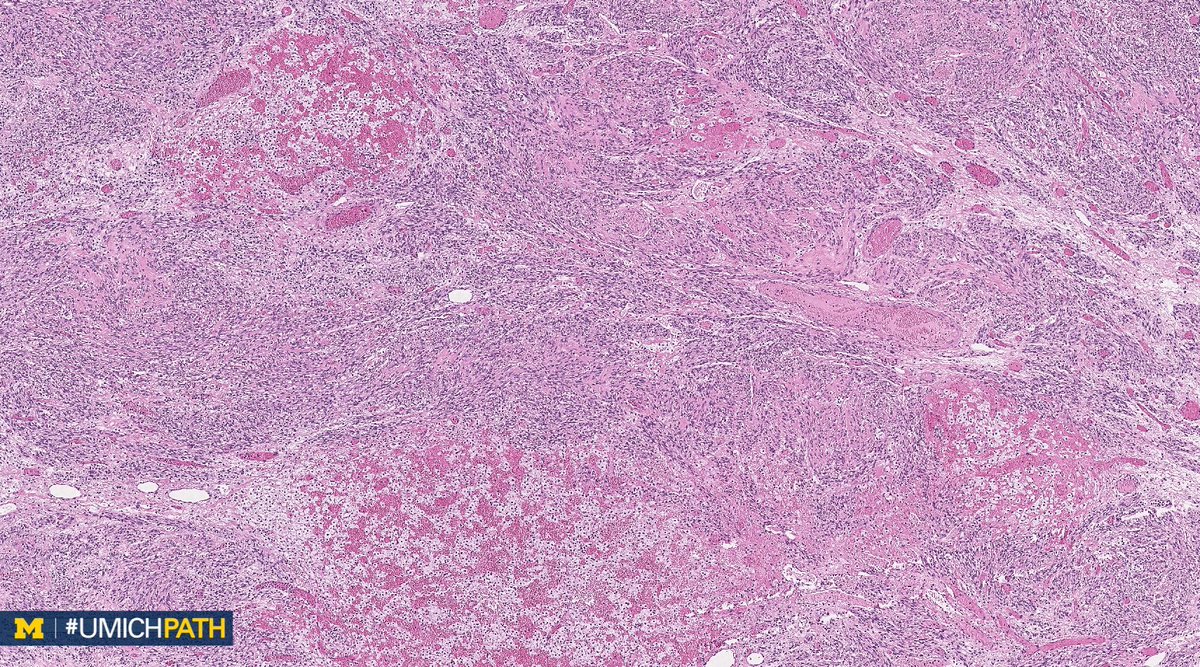

We're sharing 2 cases today since we missed #GYNPath Day 5 last week. What’s your #DailyDx of this uterine mass? We’ll tweet the answer and some quick facts tomorrow! #UMichPath

What’s your #DailyDx of this uterine mass?

We’ll tweet the answer and some quick facts tomorrow! #UMichPath

A: (Müllerian) adenosarcoma. Malignant stroma w/ associated benign epithelium (endometrioid or metaplastic); has “Phyllodes-like” architecture w/ stromal condensation. Can be low grade or have sarcomatous overgrowth (>25%) w/ high grade or heterologous sarcoma. #GYNPath #DailyDx

UMichPath's tweet image. A: (Müllerian) adenosarcoma. Malignant stroma w/ associated benign epithelium (endometrioid or metaplastic); has “Phyllodes-like” architecture w/ stromal condensation. Can be low grade or have sarcomatous overgrowth (>25%) w/ high grade or heterologous sarcoma. #GYNPath #DailyDx